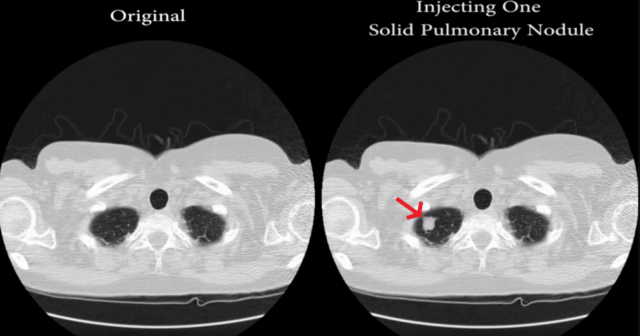

Piuttosto che limitarsi ai volti e ai gattini di cui sopra, CT-GAN è stato addestrato a generare noduli tumorali all’interno delle analisi radiologiche dello stato dei polmoni: 70 di queste analisi sono state contraffatte, quindi fornite a tre diversi radiologi che nel 99% dei casi hanno confermato la diagnosi di cancro nonostante i noduli fossero opera della IA. Sulle analisi in cui CT-GAN aveva rimosso i tumori realmente esistenti, i suddetti radiologi hanno confermato la (finta) guarigione nel 94% dei casi.

CT-GAN, questo il nome del framework malevolo ideato dagli esperti israeliani, è basato sugli algoritmi di machine learning di una rete nota come Generative Adversarial Network (GAN) – la stessa, per dire, adoperata per generare volti, gattini e altri contenuti fasulli che al momento spopolano fuori e dentro il Web.